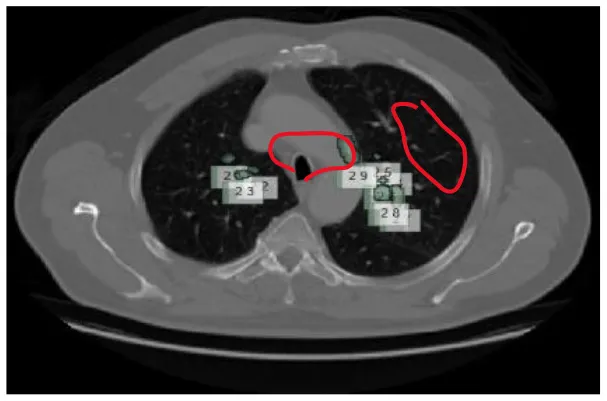

A total of 5,000 CT scans were obtained from LUNA-16. Four expert radiologists annotated the images in the LIDC/IDRI database for 2 years (20–22). Each radiologist diagnosed the nodules as non-nodules, nodules with a diameter of ≤ 3 mm, or nodules with a diameter of ≥3 mm (23). This article examines the annotation process in detail. Three of every four nodules larger than 3 mm in diameter must be identified by radiologists (24). Non-standard findings have not been noted before (non-nodules, nodules < 3 mm, and nodules annotated by only one or two radiologists). Table 2 shows various illustrations of nodules in the LUNA-16 dataset.

Table 2

| S. No. | Nodule name | Nodule image |

|---|---|---|

| 1 | Small nodule |

|

| 2 | Ground glass opacity nodule |

| 3 | Rough edged nodule |

| 4 | Thick walled nodule |

| 5 | Granular nodule |

| 6 | Pleural surface nodule |

| 7 | Pulmanory region nodule |

Various benigna and malignant nodules present in the LUNA-16 dataset.